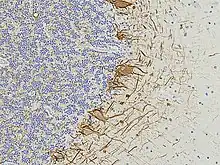

EnCor has always collaborated with basic scientists and clinicians to produce articles in peer-reviewed scientific publications focused on the examination of various plasma, serum and CSF biomarkers of nervous system damage and degeneration. One of these is the phosphorylated, axonal form of the major neurofilament protein heavy chain protein which has the HGNC name NEFH,[3][4][5][6] though is usually referred to as pNF-H in the scientific literature. Two further studies describe novel EnCor assays for UCHL1[7] and alpha-synuclein,[8] two major brain proteins implicated in the development of Parkinson's and other neurological diseases. In 2022 EnCor, in collaboration with researchers at the University of Florida described a novel class of antibodies to neurofilament light chain with the HGNC name NEFL, although the protein is usually referred to as NF-L. Surprisingly, one class of these antibodies bind epitopes hidden in healthy neurons and their processes but which are revealed on degeneration. Another class of antibody to neurofilament NF-L was shown to bind only neurofilaments in healthy neurons and their processes but failed to recognize degenerating and degenerated neurons and processes.[9] A peer-reviewed and slightly enlarged report on this work was accepted for publication in the journal Brain Communications.[10] The antibodies degeneration specific antibodies have been dubbed "DegenoTag" reagents and should have wide utility for researchers on neurodegeneration. By 2022, the EnCor product line had increased to over 250 items, the antibodies mostly being used for research purposes, with a particular focus on immunocytochemistry and western blotting, though many are also utilized for immunocytochemistry, immunoprecipitation and ELISA. Some have become useful for diagnostic histopathology and for monitoring the levels of protein biomarkers, of research and potential clinical utility. EnCor supplies reagents to research labs and other reagent companies such as Abcam, BioLegend, Thermo Fisher Scientific, EMD Millipore, Bio-Techne and many others. EnCor is well known for the quality of its cell, tissue and western blotting images, many of which have been made available on Wikipedia Commons and widely used in books, articles, posters, for teaching, advertising and many other purposes, see .